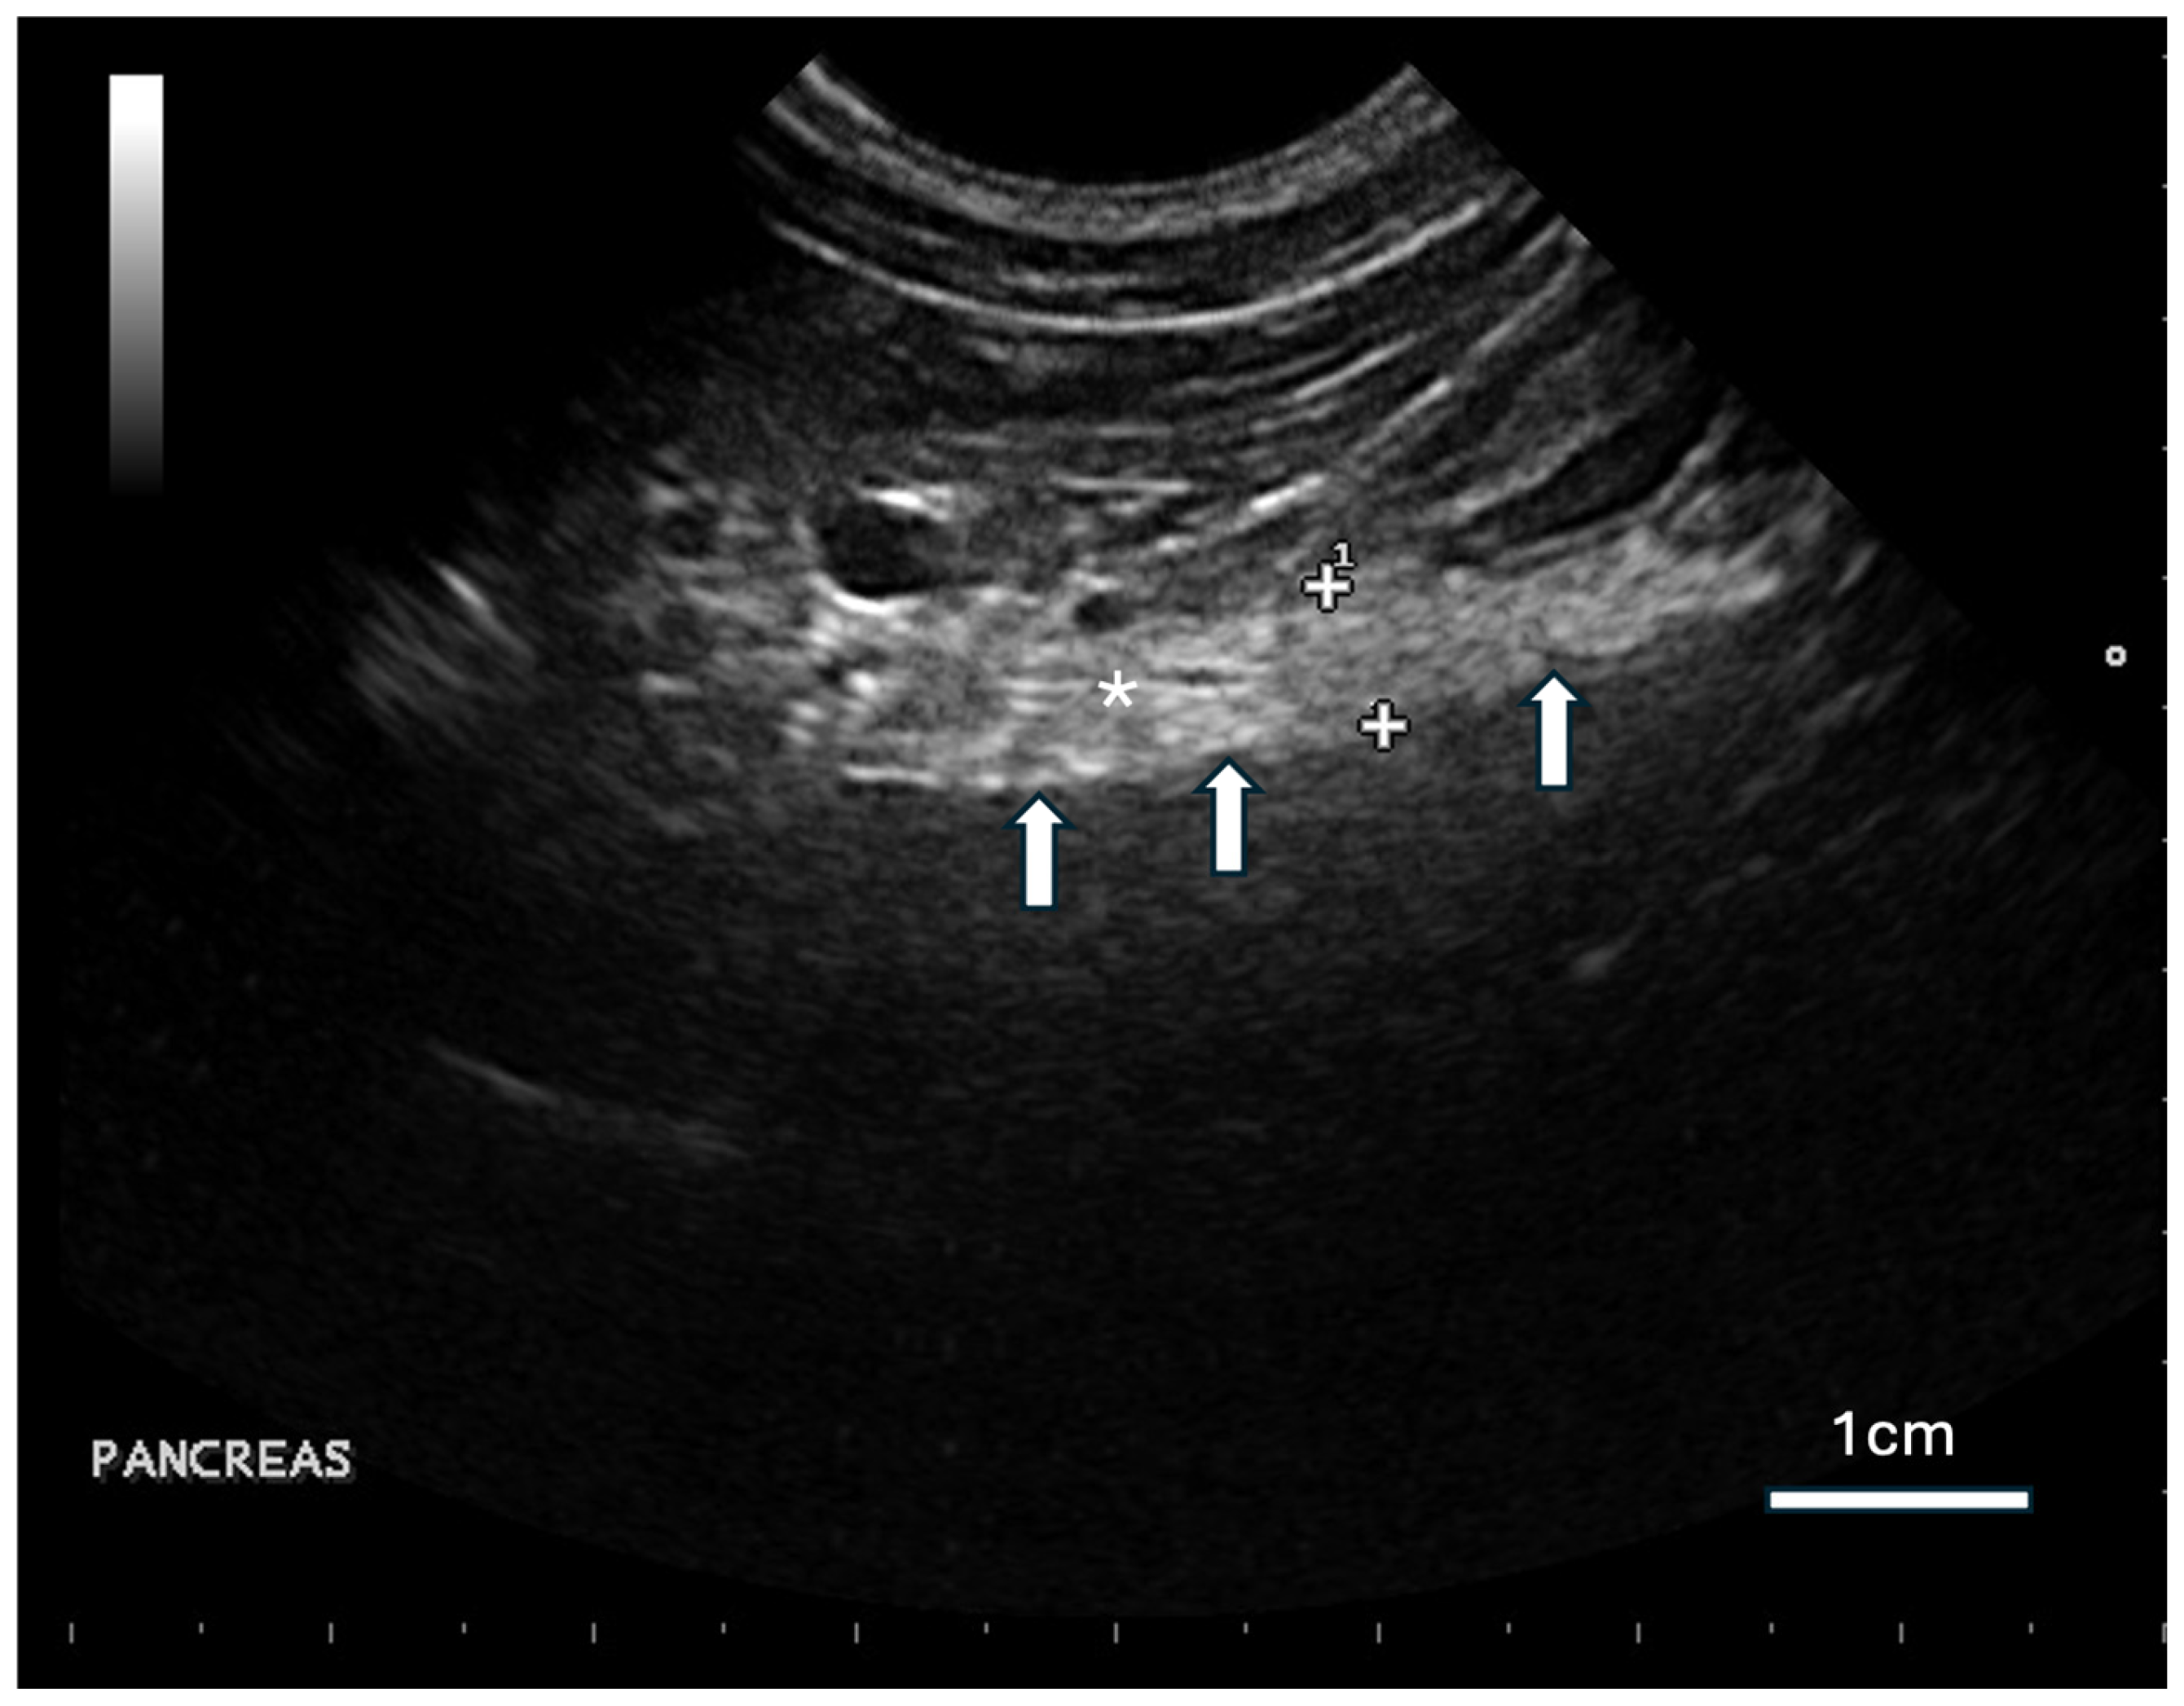

Bloodwork was repeated after 2 months (5 December 2019), in which hyperglycemia (27.71 mmol/L; RI 2.93–18.94) (

Table 1) and glucosuria (approximately >1000 mg/dL) (

Table 2) were found to be persistent. At this recheck, the binturong weighed 14.8 kg, and pancreatic changes suggestive of chronic fibrosis and suspected calcification within the pancreas were noted on ultrasonography. A generalized heterogenous hyperechogenicity and acoustic shadowing was reported in the pancreas, which appeared diffusely enlarged and irregular with rough margins (

Figure 2). A primary diagnosis of diabetes mellitus was established. Due to the logistical challenges associated with the administration of antidiabetic agents in zoological species, management at this stage was limited to changes in husbandry and diet, with increased frequency of monitoring by keepers and veterinary staff for the progression of clinical signs.

The ultrasonographic abnormalities noted in this patient were more suggestive of chronic pancreatic changes secondary to previous episodes of pancreatitis such as fibrosis or calcification, rather than amyloid deposition. This was further supported by a mild increase in serum lipase, although serum amylase remained within reference ranges, and gross changes to the pancreatic tissue were not noted on postmortem examination. In domestic animals, the use of serum lipase and amylase as stand-alone tests should be interpreted with caution due to their limited sensitivity and specificity [